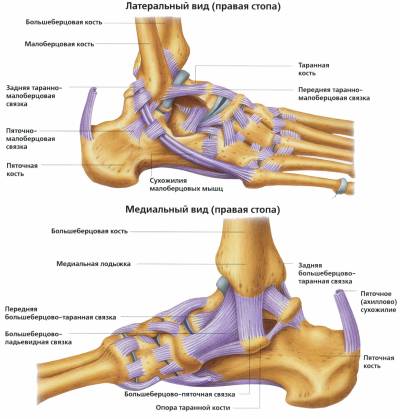

Анатомические фото голеностопного сустава и его суставных поверхностей